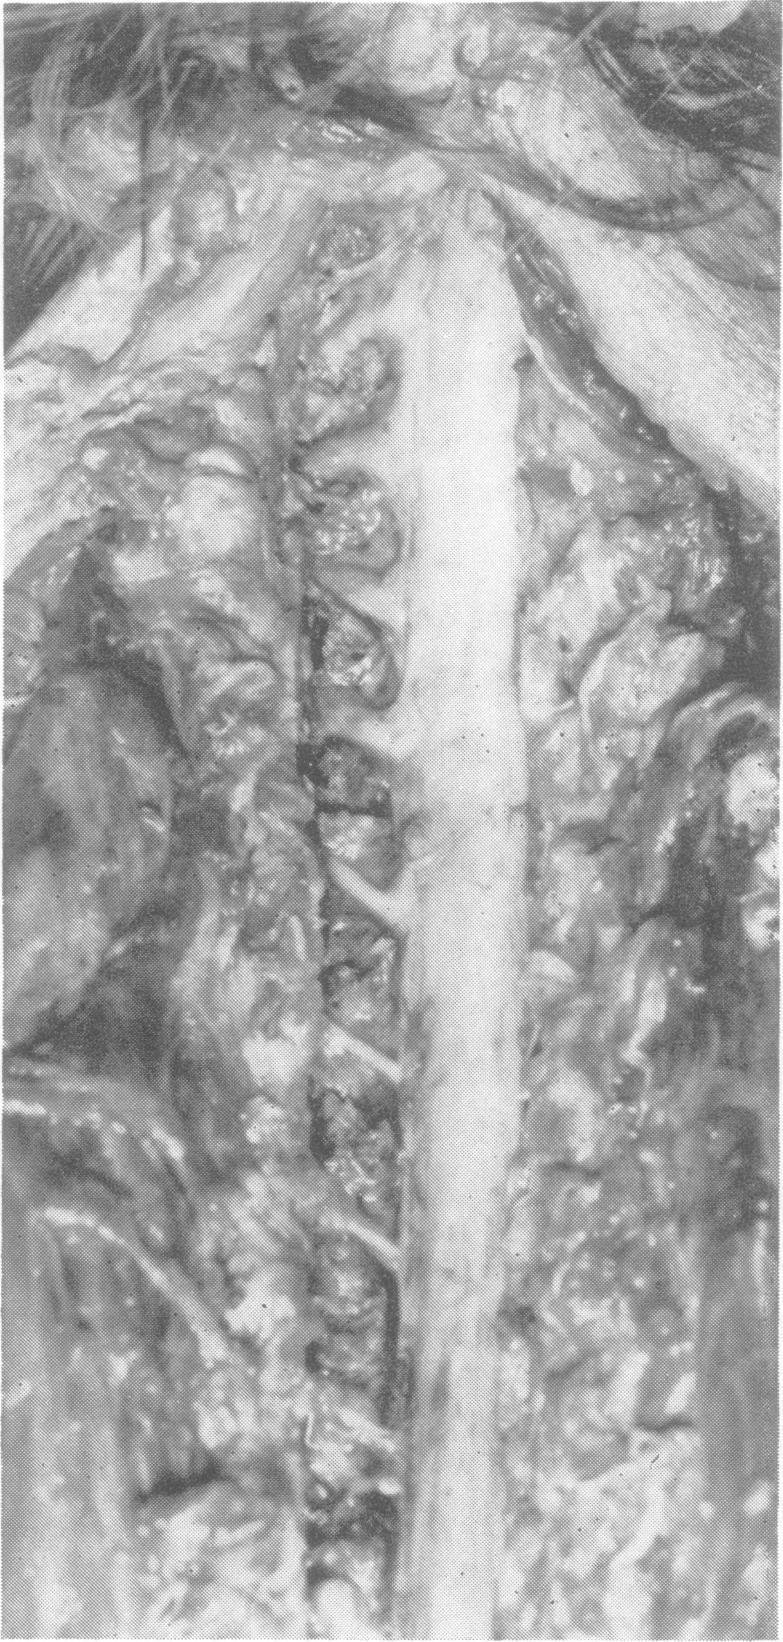

Ascending nerve roots.